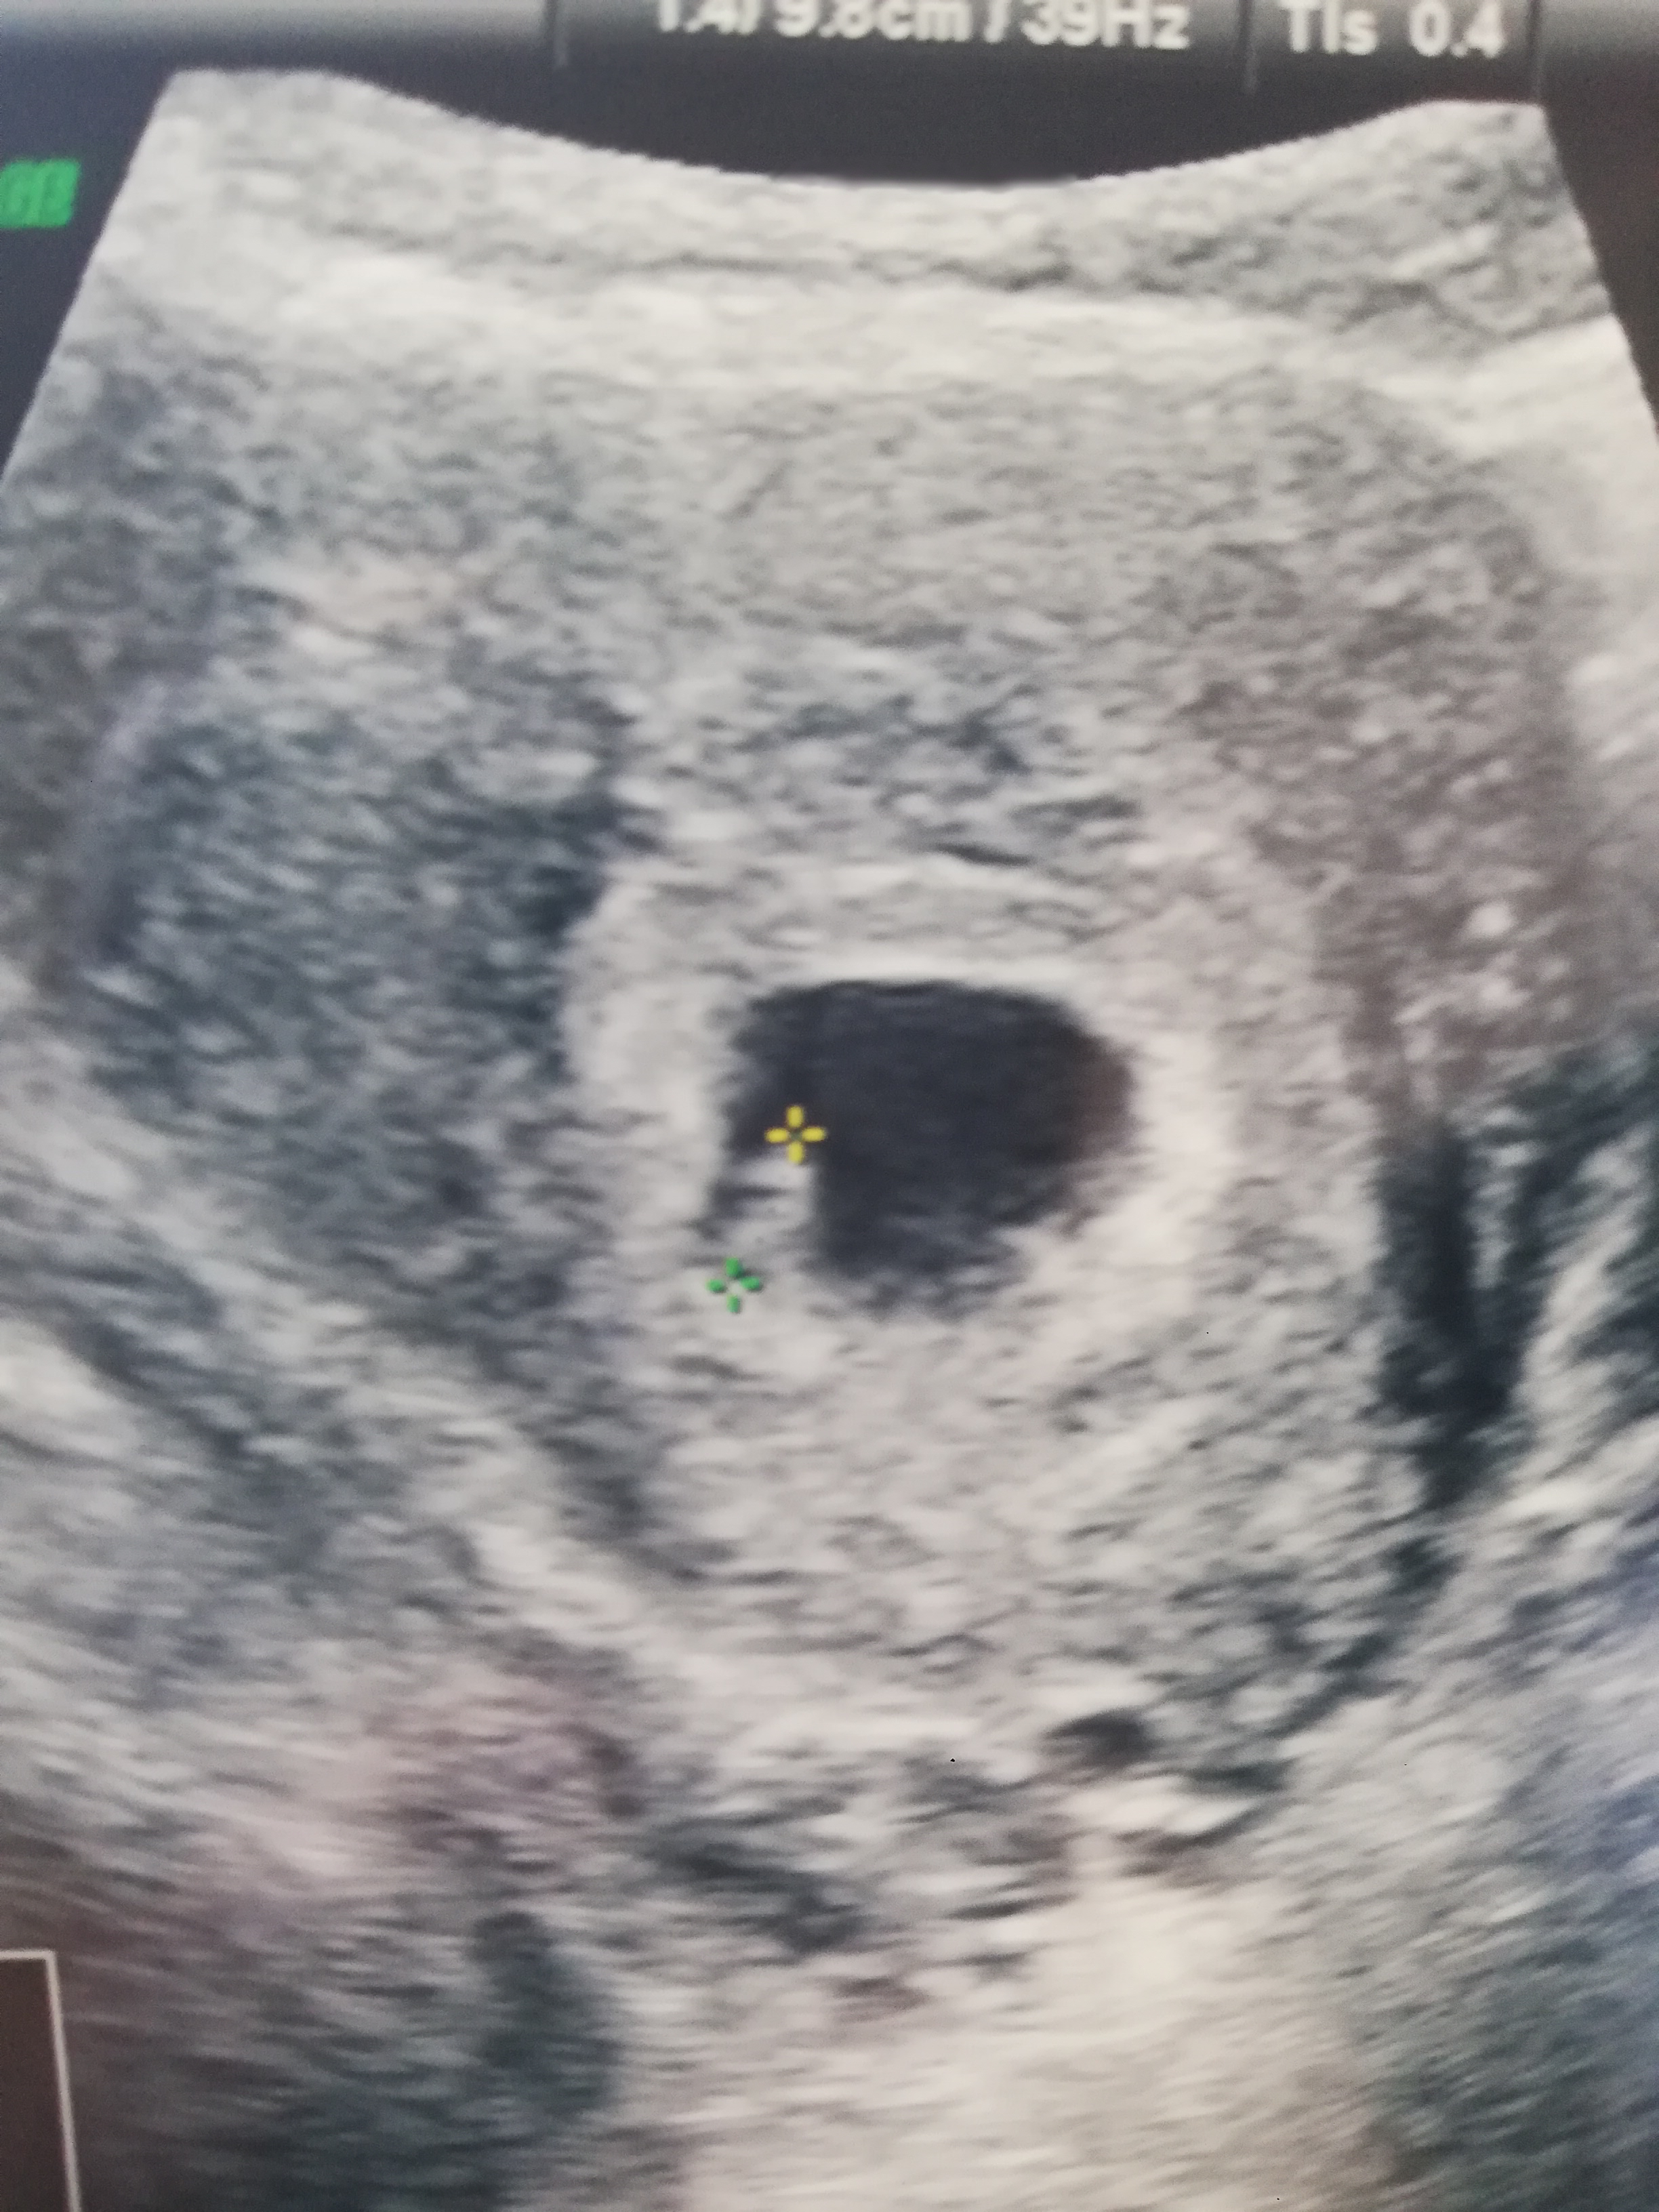

Handeee Kayıtlı Üye Katılım 4 Eylül 2021 Mesajlar 147 13 Eylül 2021 #12 SBA-' Alıntı: Erkek bu galiba sağlıkla kucağına almayı nasip etsin Genişletmek için tıkla ... Mesajınız bir önceki mesaj ile otomatik birleştirildi 13 Eylül 2021 Peki bu cinsiyet 7 haftalık Ekli dosyalar IMG_20210904_092517.jpg 4.3 MB · Görüntüleme: 232

SBA-' Alıntı: Erkek bu galiba sağlıkla kucağına almayı nasip etsin Genişletmek için tıkla ... Mesajınız bir önceki mesaj ile otomatik birleştirildi 13 Eylül 2021 Peki bu cinsiyet 7 haftalık

D DUYGUECEM Kayıtlı Üye Katılım 27 Haziran 2021 Mesajlar 123 18 Eylül 2021 #15 Handeee' Alıntı: Mesajınız bir önceki mesaj ile otomatik birleştirildi 13 Eylül 2021 Peki bu cinsiyet 7 haftalık Genişletmek için tıkla ... Erkek bence

Handeee' Alıntı: Mesajınız bir önceki mesaj ile otomatik birleştirildi 13 Eylül 2021 Peki bu cinsiyet 7 haftalık Genişletmek için tıkla ... Erkek bence